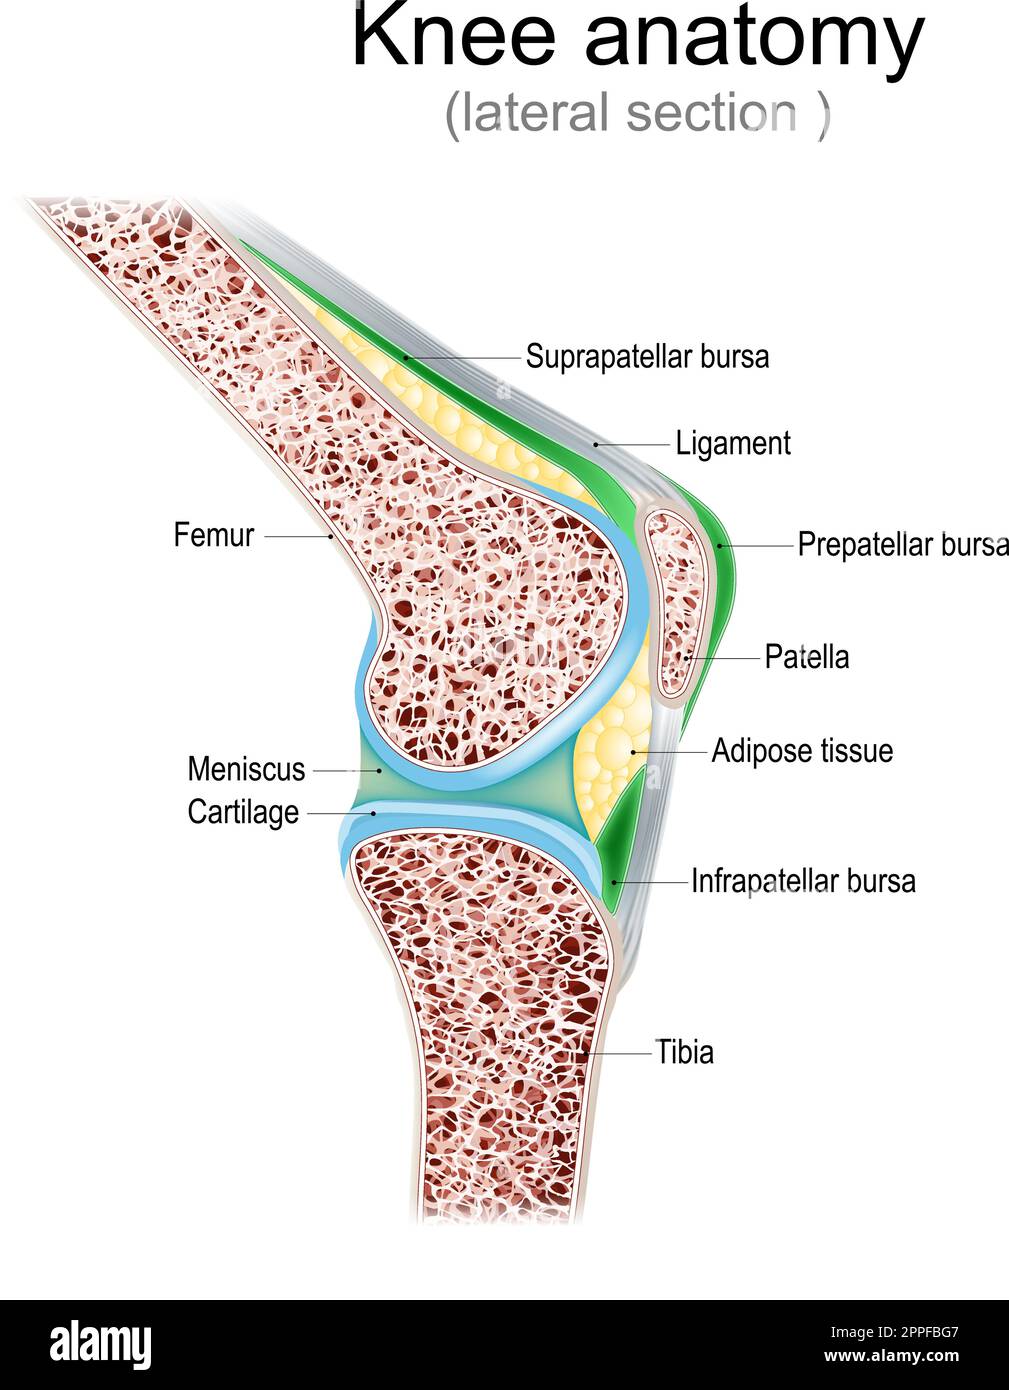

Knee anatomy. Side view. lateral section of joint with ligaments, meniscus, and bursae. knee joint cavity. Cross section of leg bones. detailed vector Stock Vectorhttps://www.alamy.com/image-license-details/?v=1https://www.alamy.com/knee-anatomy-side-view-lateral-section-of-joint-with-ligaments-meniscus-and-bursae-knee-joint-cavity-cross-section-of-leg-bones-detailed-vector-image547382199.html

Knee anatomy. Side view. lateral section of joint with ligaments, meniscus, and bursae. knee joint cavity. Cross section of leg bones. detailed vector Stock Vectorhttps://www.alamy.com/image-license-details/?v=1https://www.alamy.com/knee-anatomy-side-view-lateral-section-of-joint-with-ligaments-meniscus-and-bursae-knee-joint-cavity-cross-section-of-leg-bones-detailed-vector-image547382199.htmlRF2PPFBG7–Knee anatomy. Side view. lateral section of joint with ligaments, meniscus, and bursae. knee joint cavity. Cross section of leg bones. detailed vector